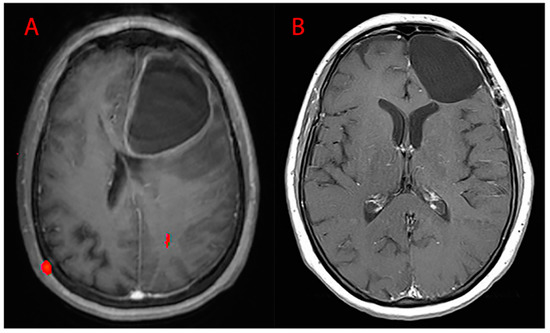

Surgery was performed by the same first operator with the aid of the following: neuronavigation system, intraoperative ultrasound, ultrasound aspirator (CUSA-CAVITRON®), thulium laser, and intraoperative neurophysiological monitoring. Of the procedures, 19.40% were conducted in awake surgery so as to monitor, real-time, the functions of the patient during surgery in eloquent areas. GTR (Figure 9) was performed in 85.95% of cases, while STR (Figure 10) in the residual 14.05%. Partial resections (resection < 90%) and biopsies were not included. Our follow-up consisted of radiological evaluation through brain MRI with gadolinium 20 days after surgery and subsequent clinical reevaluation. Cases of recurrence were also treated in our department: 66.54% of patients underwent a second procedure and 24.95% underwent three.

Figure 10.

MRI T1WI axial sections. (A) Preoperative left parieto-occipital GBM and (B) postoperative images (EOR = 90%–100%, STR).